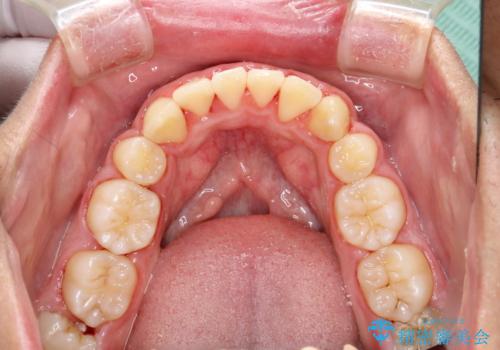

ワイヤー矯正終了時に装置除去と合わせてPMTC

- ワイヤー矯正の終了時にしばらく行っていないためクリーニングも希望されました。装置の除去j時にPMTC60分コースを行いました。

装置を除去すると、エナメル質にダメージがかかることなどがあります。除去の際、一緒にクリーニングを行うことで、エナメル質をなめらかにしたり、歯ぐきの引き締まりが見られます。また、歯ブラシだけでは取り除けない汚れも取り除きますので、歯の表面がツルツルになります。矯正治療中・終了時には合わせてPMTCを行うことがおすすめです。